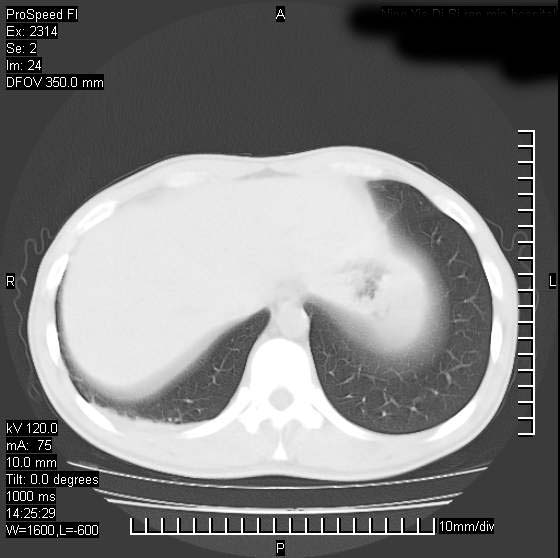

男性,再生障碍性贫血,入院前发热10天,最高40c,右侧胸痛,外院ct示右上,中肺边缘模糊的球性影(就是我现在图中标示的范围),考虑炎症,在我院使用头孢呋辛,洛美沙星10天,高烧消退,自感下午稍有发热,但今天ct示右上,中肺病灶明显扩大,还是考虑炎症,看其中的球型影是否霉菌感染??,是否能排除结核?

右肺中叶外侧段病变,上缘界限不清,下缘锐利,以段性发病为主,内见巨大空洞及空洞内容物,结合病史首先考虑:化脓性肺炎。不除外霉菌感染!

考虑霉菌感染.理由1\\有临床基础疾病,2\\有坏死的空腔,其内可见软组织影.

片状高密度影内见空洞影,内可见球形软组织密度影,并有新月征,考虑霉菌感染.